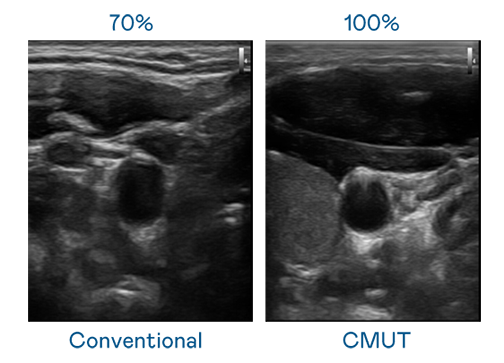

CMUT 技术是一种用电容式微机电元件来产生超音波讯号的技术。与传统 PZT 压电式技术相比,CMUT 频宽增加 30%,更宽频的超音波讯号让影像解析度大幅提升,是实现高影像品质医疗超音波扫描、促进精准医疗发展的关键技术。

大频宽带来超清晰影像

超音波影像的解析度高低,首先取决于探头能发出的讯号频宽。非凡娱乐 CMUT 可提供高清晰的超音波讯号,提供高频宽、高灵敏度、影像纹理细节更高的超音波影像,协助医护人员缩短影像判读时间及利用精准的医疗影像进行诊断。